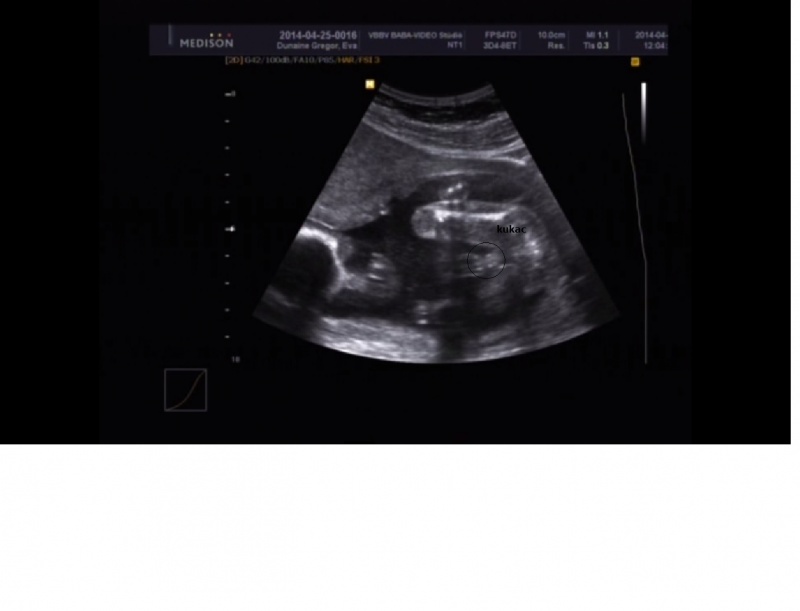

Egy élő magzat, medencevégű fekvésben.

NB:6,9 mm(normál érték), Prenasalis rés:1,7 mm (normál érték). Jó életjelenségek, normál magzatmozgások, ritmusos szívműködés. FHR: 144/min. A biometriai adatok 18 hetes 5 napos graviditáshoz tartoznak.